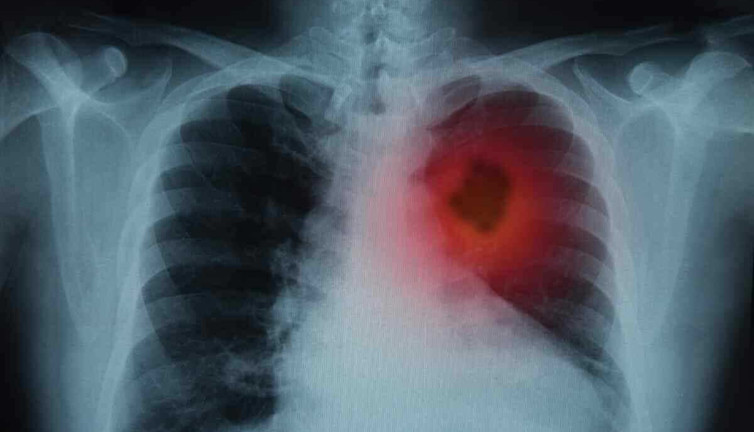

Doktorlar 1 yıl ömür biçmişti. Kanser akciğerlerine göğüs kemiğine ve lenf bezlerine yayılmıştı ABD'de kanserin akciğerlerine, göğüs kemiğine ve lenf bezlerine yayıldığını gören doktorlar 51 yaşındaki Jasmin David'e 1 yıl ömür biçmişti. Bir klinik deneyde yer alan kadın, yapılan iğne ve verilen ilaçtan sonra kanserden tamamen kurtuldu.

Korona virüsün paramparça ettiği organı açıkladı. Bilim Kurulu Üyesi uyarı üstüne uyarı yaptı Sağlık Bakanlığı Korona virüs Bilim Kurulu Üyesi Doç. Dr. Sema Turan, "Virüsün yarattığı akciğer hasarı inanılmaz. Bir yoğun bakım hekimi olarak söyleyebilirim ki gördüğümüz akciğer filmleri ve tomografileri olayın şiddetinin oldukça fazla olduğunu ve bu hasta gruplarının da zannedildiği gibi çok ileri yaş olmadığını söylemek zorundayım’’ dedi.